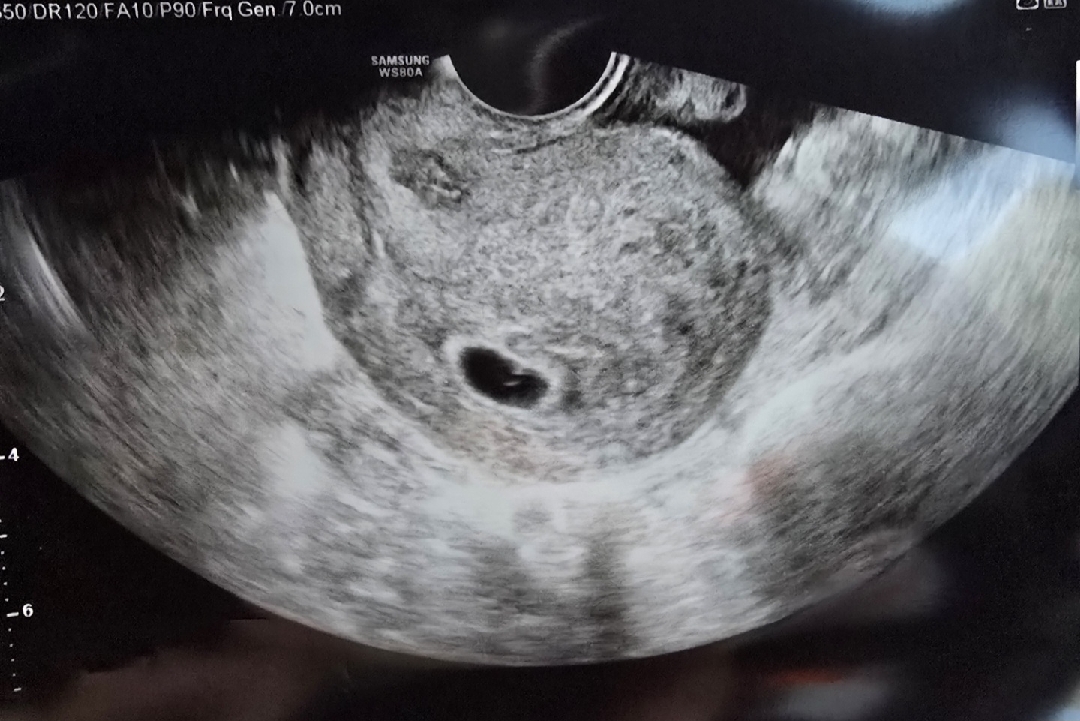

10월2일에 이식하고 저번주에 아기집 확인하고 화요일에 난황보구왔어요 아기집 크기는 1.29cm예요 아기집도 작다공... 6주3일인데 저는 착상이 늦게되어서 5주3일이라고 했어요ㅜㅜ 다음주엔 꼭 심장이 뛰어야 한다고 하던데 하루하루가 피가 말라용~~ 저처럼 착상이 늦어서 일주일정도 차이나신분 계셔요? 아가 건강히 잘크고 있나요? 남들은 가벼운 운동도하고 그러는데 저는 12주까지는 최대한 안움직일려구용~~

정말요? 감사해요 맘이 놓이네요 저번주에 아기집만보였을때 0.99였는데 그때도 아기집이 작다 하셨거든요 기준을 모르겠어요 그래도 리주아주아님 아가 잘크고 있다니 저도 좋은생각만 해야겠어요 감사합니다